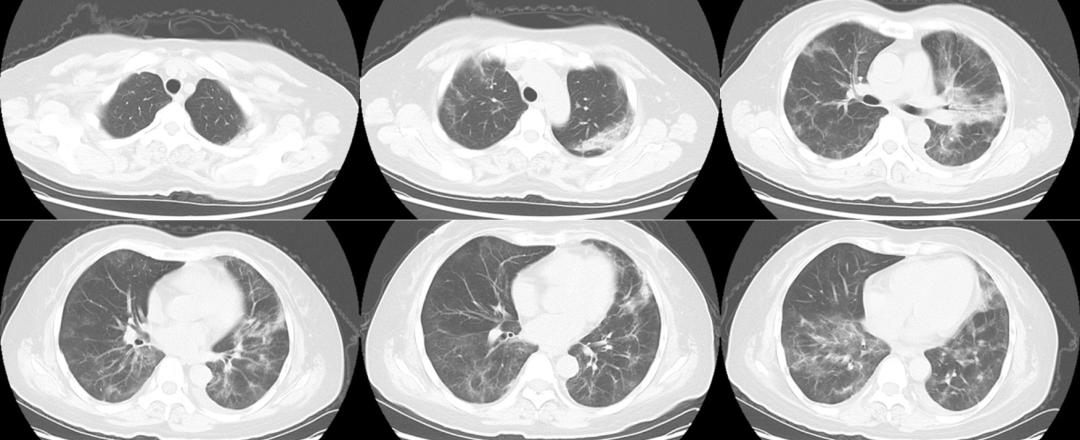

图2 胸部CT平扫(2023年3月3日)

胸部CT:双肺多发斑片、磨玻璃密度影,部分较前新发,部分病变吸收。